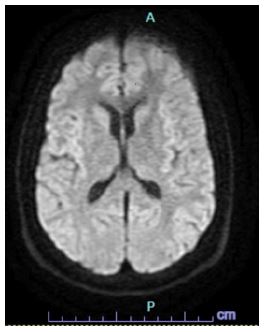

While in the ICU, the patient improved and did not have any further acute neurological events. Initial lab work on presentation showed normal CMP and troponins, and was pertinent for atypical lymphocytes, transaminitis. Daily labs showed a mild thrombocytopenia, improvement in the transaminitis, a normal urinalysis, and a negative urine drug screen. Daily labs on the date of discharge showed a mild thrombocytopenia and transaminitis. Neurology recommended an EEG which showed mild diffuse slowing with asymmetry and an MRI which showed no acute infarct or hemorrhage, midline shift, mass effect or evidence of acute ischemic stroke (Figure 4). Infectious disease recommended empiric vancomycin, ceftriaxone and acyclovir and virology was done confirming a positive EBV infection. Due to the patient’s symptomatic improvement, lumbar puncture was not done. Cardiology recommended 2D-echocardiogram with bubble study to rule out embolic stroke which showed a normal cardiac status. Gastroenterology was consulted due to mild transaminitis likely secondary to infectious mononucleosis and recommended a RUQ ultrasound, showing a 4 cm echogenic lesion in the right lobe (Figure 5). Over the course of the patient’s admission in the ICU, the patient did not endorse any neurological or cardiac complaints, reporting only a mild headache and vomiting with normal serial neurological exams.

Figure 4: MRI.